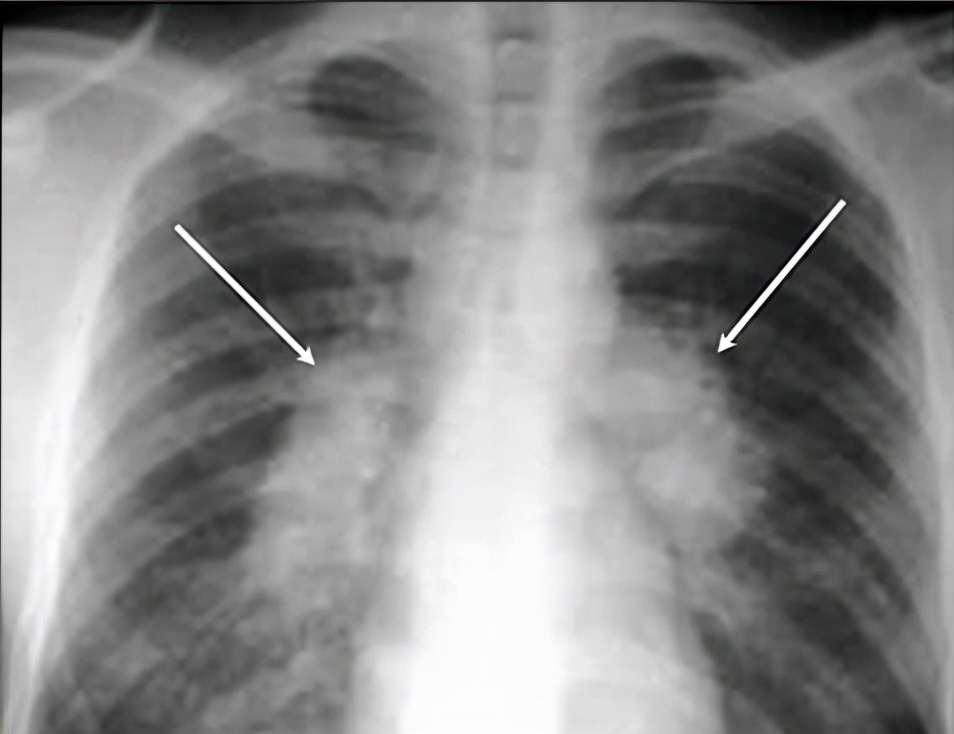

01 X线检查

所谓的X射线检查,就是利用X射线穿透患者的身体并形成影像跟拍照片的原理差不多,其拍摄出的图像是平面状态。

根据临床调查表明,每做一次X线检查辐射剂量约是0.02~0.1mSv,就如同患者坐飞机连续飞行20小时接受的辐射一般。

即便是每个人在日常生活中,每年所接收到的自然辐射,也将近约有2.0~3.0mSv,所以X线检查并不会对机体造成影响。

优点: 快捷、价廉。

缺点: 受制于深浅组织的影像相互重叠和隐藏,有时需要多次多角度拍摄X光片才能看清。